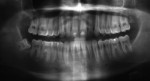

Five cases met the criteria as set forth in the study and are summarized in Table 1; radiographs of the five cases are shown in Figure 1 through Figure 21. Ages ranged from 15 to 48 years. Four patients were male and one female. All five cases involved Caucasian patients. Two cases involved the distal roots of mandibular first molars bilaterally (Figure 1, Figure 2, Figure 3, Figure 4, Figure 5, Figure 6, Figure 7, Figure 8, and Figure 18, Figure 19, Figure 20, and Figure 21); one case involved both roots of the mandibular first molars bilaterally (Figure 11, Figure 12, Figure 13, Figure 14); and two cases involved the mandibular second premolar unilaterally (Figure 9 and Figure 10, and Figure 15, Figure 16, and Figure 17). Two of the patients presented with symptoms similar to cracked-tooth syndrome (Table 1, Case 3 and Case 4), one with “chronic reversible pulpitis” (Table 1, Case 1), and two were asymptomatic (Table 1, Case 2 and Case 5).

Patients in all five cases exhibited PARR of the involved roots, as previously described (Figure 1 through Figure 21).40 The roots showed shortening and blunting of the apex of greater than 2 mm in all five cases. In three of the five cases, the PARR self-arrested without any treatment. The mandibular left first molar in Case 1 (Figure 5, Figure 6, Figure 7, and Figure 8) received conventional root canal therapy (RCT), while the mandibular right first molar in Case 3 (Figure 11, Figure 12, Figure 13, Figure 14) received a bonded ceramic crown. The PARR appears to have arrested in these two cases, and the outcome of the treatment in relation to the resorption could not be determined. The symptoms the patients were experiencing did eventually resolve. Consequently, all five study cases became symptom-free, including the patient who received conventional RCT (Case 1).

The Case 1 patient, who was the son of the Case 2 patient, was observed in preoperative orthodontic records prior to initiating orthodontic therapy (Figure 1 and Figure 2). The Case 1 patient also demonstrated PARR of the mandibular anterior incisors post-orthodontic therapy (Figure 8). The Case 5 patient had serial extractions completed as a child, but no fixed or removable orthodontic appliances were utilized. Past medical histories were all noncontributory (Table 1). No cases of MICR or MIAR were identified in any of the files reviewed.

The radiologic feature of PARR is characteristic of LIAR. PARR was readily apparent in all five cases (Figure 1 through Figure 21). Two or more millimeters of apical root were resorbed and replaced with normal-appearing trabeculated bone. The PDL space and remnants of the lamina dura appeared to be intact. The apical root canal space appeared patent but somewhat narrowed. The teeth were not ankylosed. Conversely, PARR due to trauma results in ankylosis with bone replacement resorption from both the apical and lateral directions of the root with obliteration of the root canal space and PDL space.1,40-42 PARR from orthodontics would be impossible to distinguish from LIAR radiographically; however, a history of prior orthodontics and the location of the involved teeth would separate this process from LIAR (Table 2).